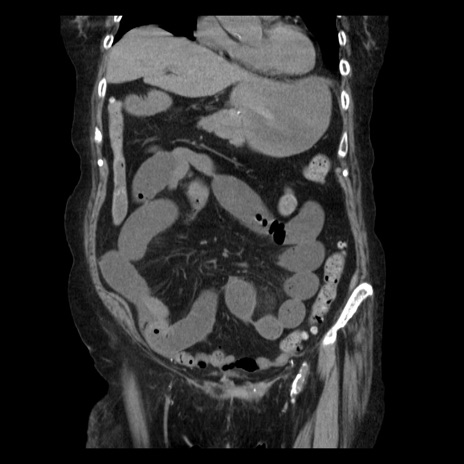

横断像

【症例】 90歳代女性

【主訴】 腹痛・嘔吐

【現病歴】今朝から左側腹部痛を認めた。 経過観察していたが、嘔吐を認めたため来院。

【既往歴】 子宮癌術後

【身体所見】 意識清明、BP 127/54mmHg、P 98bpm Sp02 95%(RA)、BT 35.8°C、腹部平坦・軟腸ぜん動音聴取良好、右下腹部圧痛(+) 反跳痛なし

【データ】WBC 9800、CRP 0.46